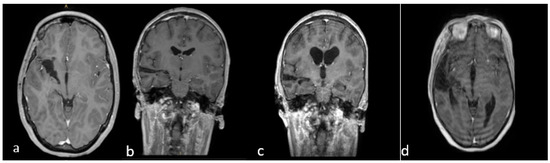

Thalamopeduncular tumors are lesions that arise at the junction between the thalamus and the cerebral peduncles [1] (Figure 4). Most of these tumors are slow-growing pilocytic astrocytoma and displaced the corticospinal bundle, leading to the typical contralateral progressive spastic hemiparesis described as “childhood thalamopeduncular syndrome” [11].

Preoperative brain MRI of the thalamopeduncular tumor of Case A (a,b) and of Case B (c,d). (a,b) Brain MRI, T1-weighted with gadolinium, showing solid-cystic right thalamopeduncular tumors in the axial plane (on the left) and coronal plane (on the right) in Case A. (c,d) Brain MRI, T1-weighted with gadolinium, showing a right thalamopeduncular lesion with disomogenous contrast enhancement in the axial (on the left) and coronal (on the right) plane in Case B.